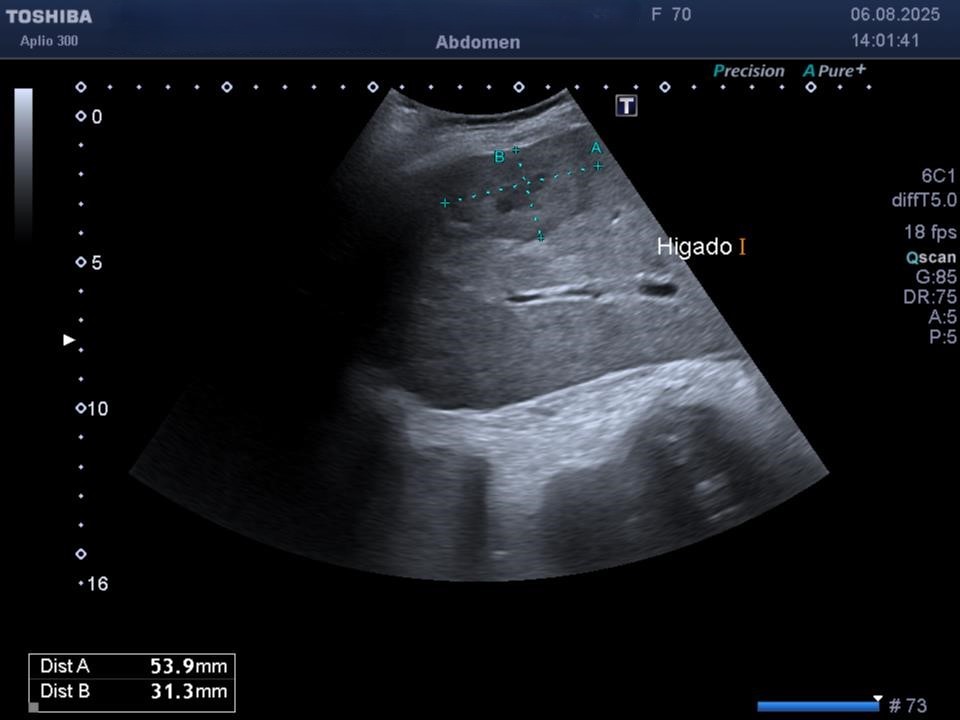

Se realiza una ecografía abdominal en la que se puede ver el hígado aumentado de tamaño, con parénquima heterogéneo y varias imágenes en forma de donut altamente sugestivas de metástasis hepáticas.